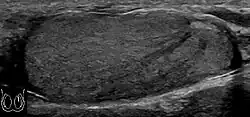

Patients with testicular lymphoma are usually old aged around 60 years of age, present with painless testicular enlargement and less commonly with other systemic symptoms such as weight loss, anorexia, fever and weakness. Bilateral testicle involvements are common and occur in 8.5% to 18% of cases. At sonography, most lymphomas are homogeneous and diffusely replace the testis [Fig. 7]. However focal hypoechoic lesions can occur, hemorrhage and necrosis are rare. At times, the sonographic appearance of lymphoma is indistinguishable from that of the germ cell tumors [Fig. 8], then the patient's age at presentation, symptoms, and medical history, as well as multiplicity and bilaterality of the lesions, are all important factors in making the appropriate diagnosis.

Primary leukemia of the testis is rare. However, due to the presence of blood-testis barrier, chemotherapeutic agents are unable to reach the testis, hence in boys with acute lymphoblastic leukemia, testicular involvement is reported in 5% to 10% of patients, with the majority found during clinical remission. The sonographic appearance of leukemia of the testis can be quite varied, as the tumors may be unilateral or bilateral, diffuse or focal, hypoechoic or hyperechoic. These findings are usually indistinguishable from that of the lymphoma [Fig. 9].

Fig. 9. Leukemia. Diffuse hypoechoic infiltrative lesions are seen involving the whole testis, indistinguishable from that of the lymphoma.